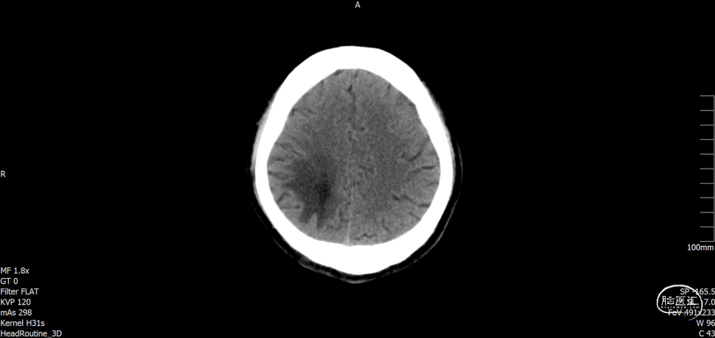

术后随访

术后72h CT,复查后拔除硬膜下引流管

术后72h胸部 CT

术后1周 CT

术后70天CT